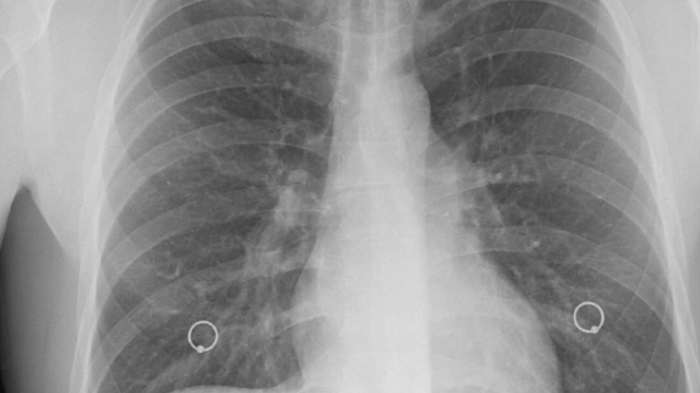

診斷肺部纖維化,通常需要多管齊下。醫生會先問病史,然後做身體檢查,聽聽肺部有沒有異常聲音。接著可能安排影像學檢查,像胸部X光或高解析度電腦斷層掃描(HRCT),後者更能看清楚纖維化的細節。

肺功能測試也很重要,可以測量肺活量和氣體交換能力。有時還會做血液檢查或支氣管鏡檢,排除其他疾病。整個過程可能花點時間,但準確診斷是治療的第一步。